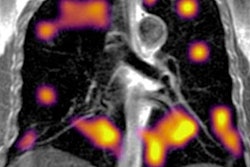

CT features at baseline, and one-year follow-up, in a 30-year-old woman who developed severe COVID-19 pneumonia (intubation, 40 days in intensive care unit). a,b: Baseline CT showing extensive ground glass opacities (GGOs) and consolidation. c–g: 1-year CT follow-up. Residual GGO, with a linear shape, is mainly seen in the upper lung, suggestive of organizing pneumonia at a late phase. There is no bronchial dilatation, signs of architectural distortion, or honeycombing, as confirmed by minimum intensity projections (minIP) (e, f, g). The sagittal minIP reformations (f, g) demonstrate plurilobular areas of decreased attenuation (arrows). This mosaic attenuation pattern might be due to either residual small airway disease or peripheral vascular obstruction. Decreased diffusing capacity (DLCO) at one year was 64%.The report devotes a section to the role of CT pulmonary angiography (CTPA) and dual-energy CT (DECT). DECT enables assessment of pulmonary perfusion and the detection of capillary microvascular thrombosis.

"If validated in larger series, DECT might be used in patients with persisting abnormal gas exchange despite apparent normalization of lung parenchyma on CT," the authors wrote. "To date, there is no evidence in the literature that macrovascular disease plays a role in long COVID or post-COVID syndrome."

It is unclear if there are still peripheral perfusion deficits in the late follow-up, so CTPA is only suggested if there is further evidence of pulmonary embolism following the general consideration of pretest probability and D-dimers, especially if supplementary oxygen is needed in patients with limited disease extension. Also, CTPA can be considered in the follow-up of patients who had PE in the acute phase of the disease, they noted.